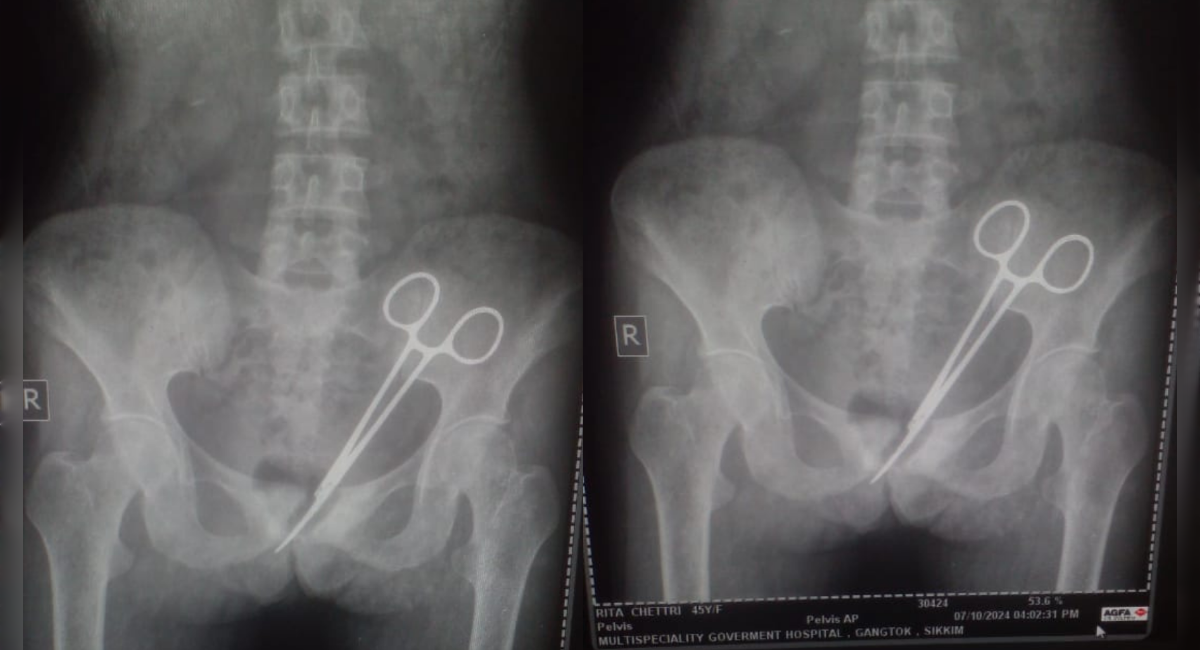

సిక్కిం రాష్ట్రానికి చెందిన ఓ మహిళ 12 ఏళ్ల క్రితం గ్యాంగ్‌టక్‌లోని ఓ ఆసుపత్రిలో అపెండిక్స్ శస్త్ర చికిత్స చేయించుకుంది. అప్పటి నుండి ఆ మహిళ తరచుగా కడుపునొప్పితో ఇబ్బంది పడుతూ వచ్చింది. చాలా మంది వైద్యులను సంప్రదించినప్పటికీ నొప్పి తగ్గలేదు. నొప్పికి కారణం కూడా చెప్ప లేకపోయారు. అయితే ఈ నెల 8న ఆమె తనకు గతంలో శస్త్ర చికిత్స చేసిన ఆసుపత్రికి వెళ్లి వైద్యులను సంప్రదించగా, వారు అనుమానంతో ఎక్స్‌రే తీయగా కళ్ళు తిరిగి దృశ్యాలు బయట పడ్డాయి.

ఆమె పొత్తి కడుపులో రెండు సర్జికల్ కత్తెరలు ఉన్నట్లు గుర్తించారు. దీంతో వెంటనే ఆ మహిళకు శస్త్ర చికిత్స చేసి ఆ రెండు కత్తెరలను తొలగించారు. ఆమె ప్రస్తుతం కోలుకుంటోందని వైద్యులు వెల్లడించా

రు.